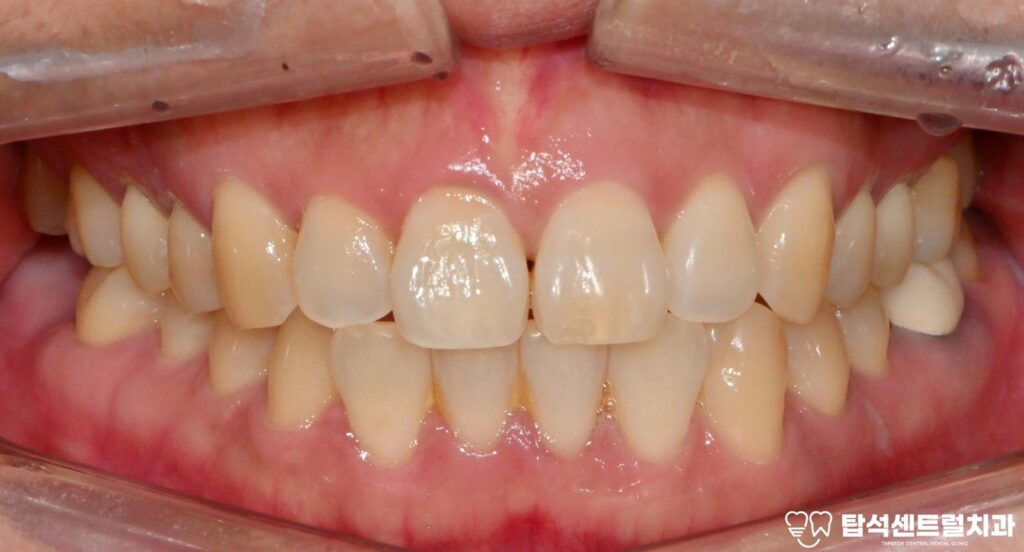

케이스의 경우에는, 아래턱에

임플란트를 식립할 예정입니다.

잇몸뼈의 상태를 확인한 모습입니다.

잇몸 뼈가 남아 있는 양에 따라,

뼈이식의 필요 유무가 정해집니다.